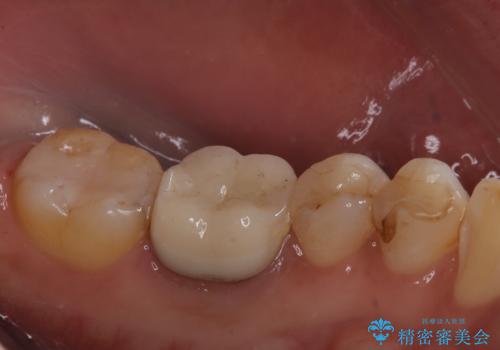

銀歯がとれた セラミックインレーで修復

- 銀歯が取れたとのことで来院されました。

拡大鏡下で丁寧に虫歯を取り除き、セラミックインレーによる修復治療を行いました。

銀歯を固着するセメントは経年劣化し溶け、隙間ができます。そこにプラークが侵入して虫歯が再発します。今回のように銀歯が脱離してしまうこともあります。

今回は銀歯が取れたので、虫歯が神経まで達して痛みが出る前に、強度・審美に優れ、虫歯の再発の少ないセラミックインレーにて治療を行うことができました。